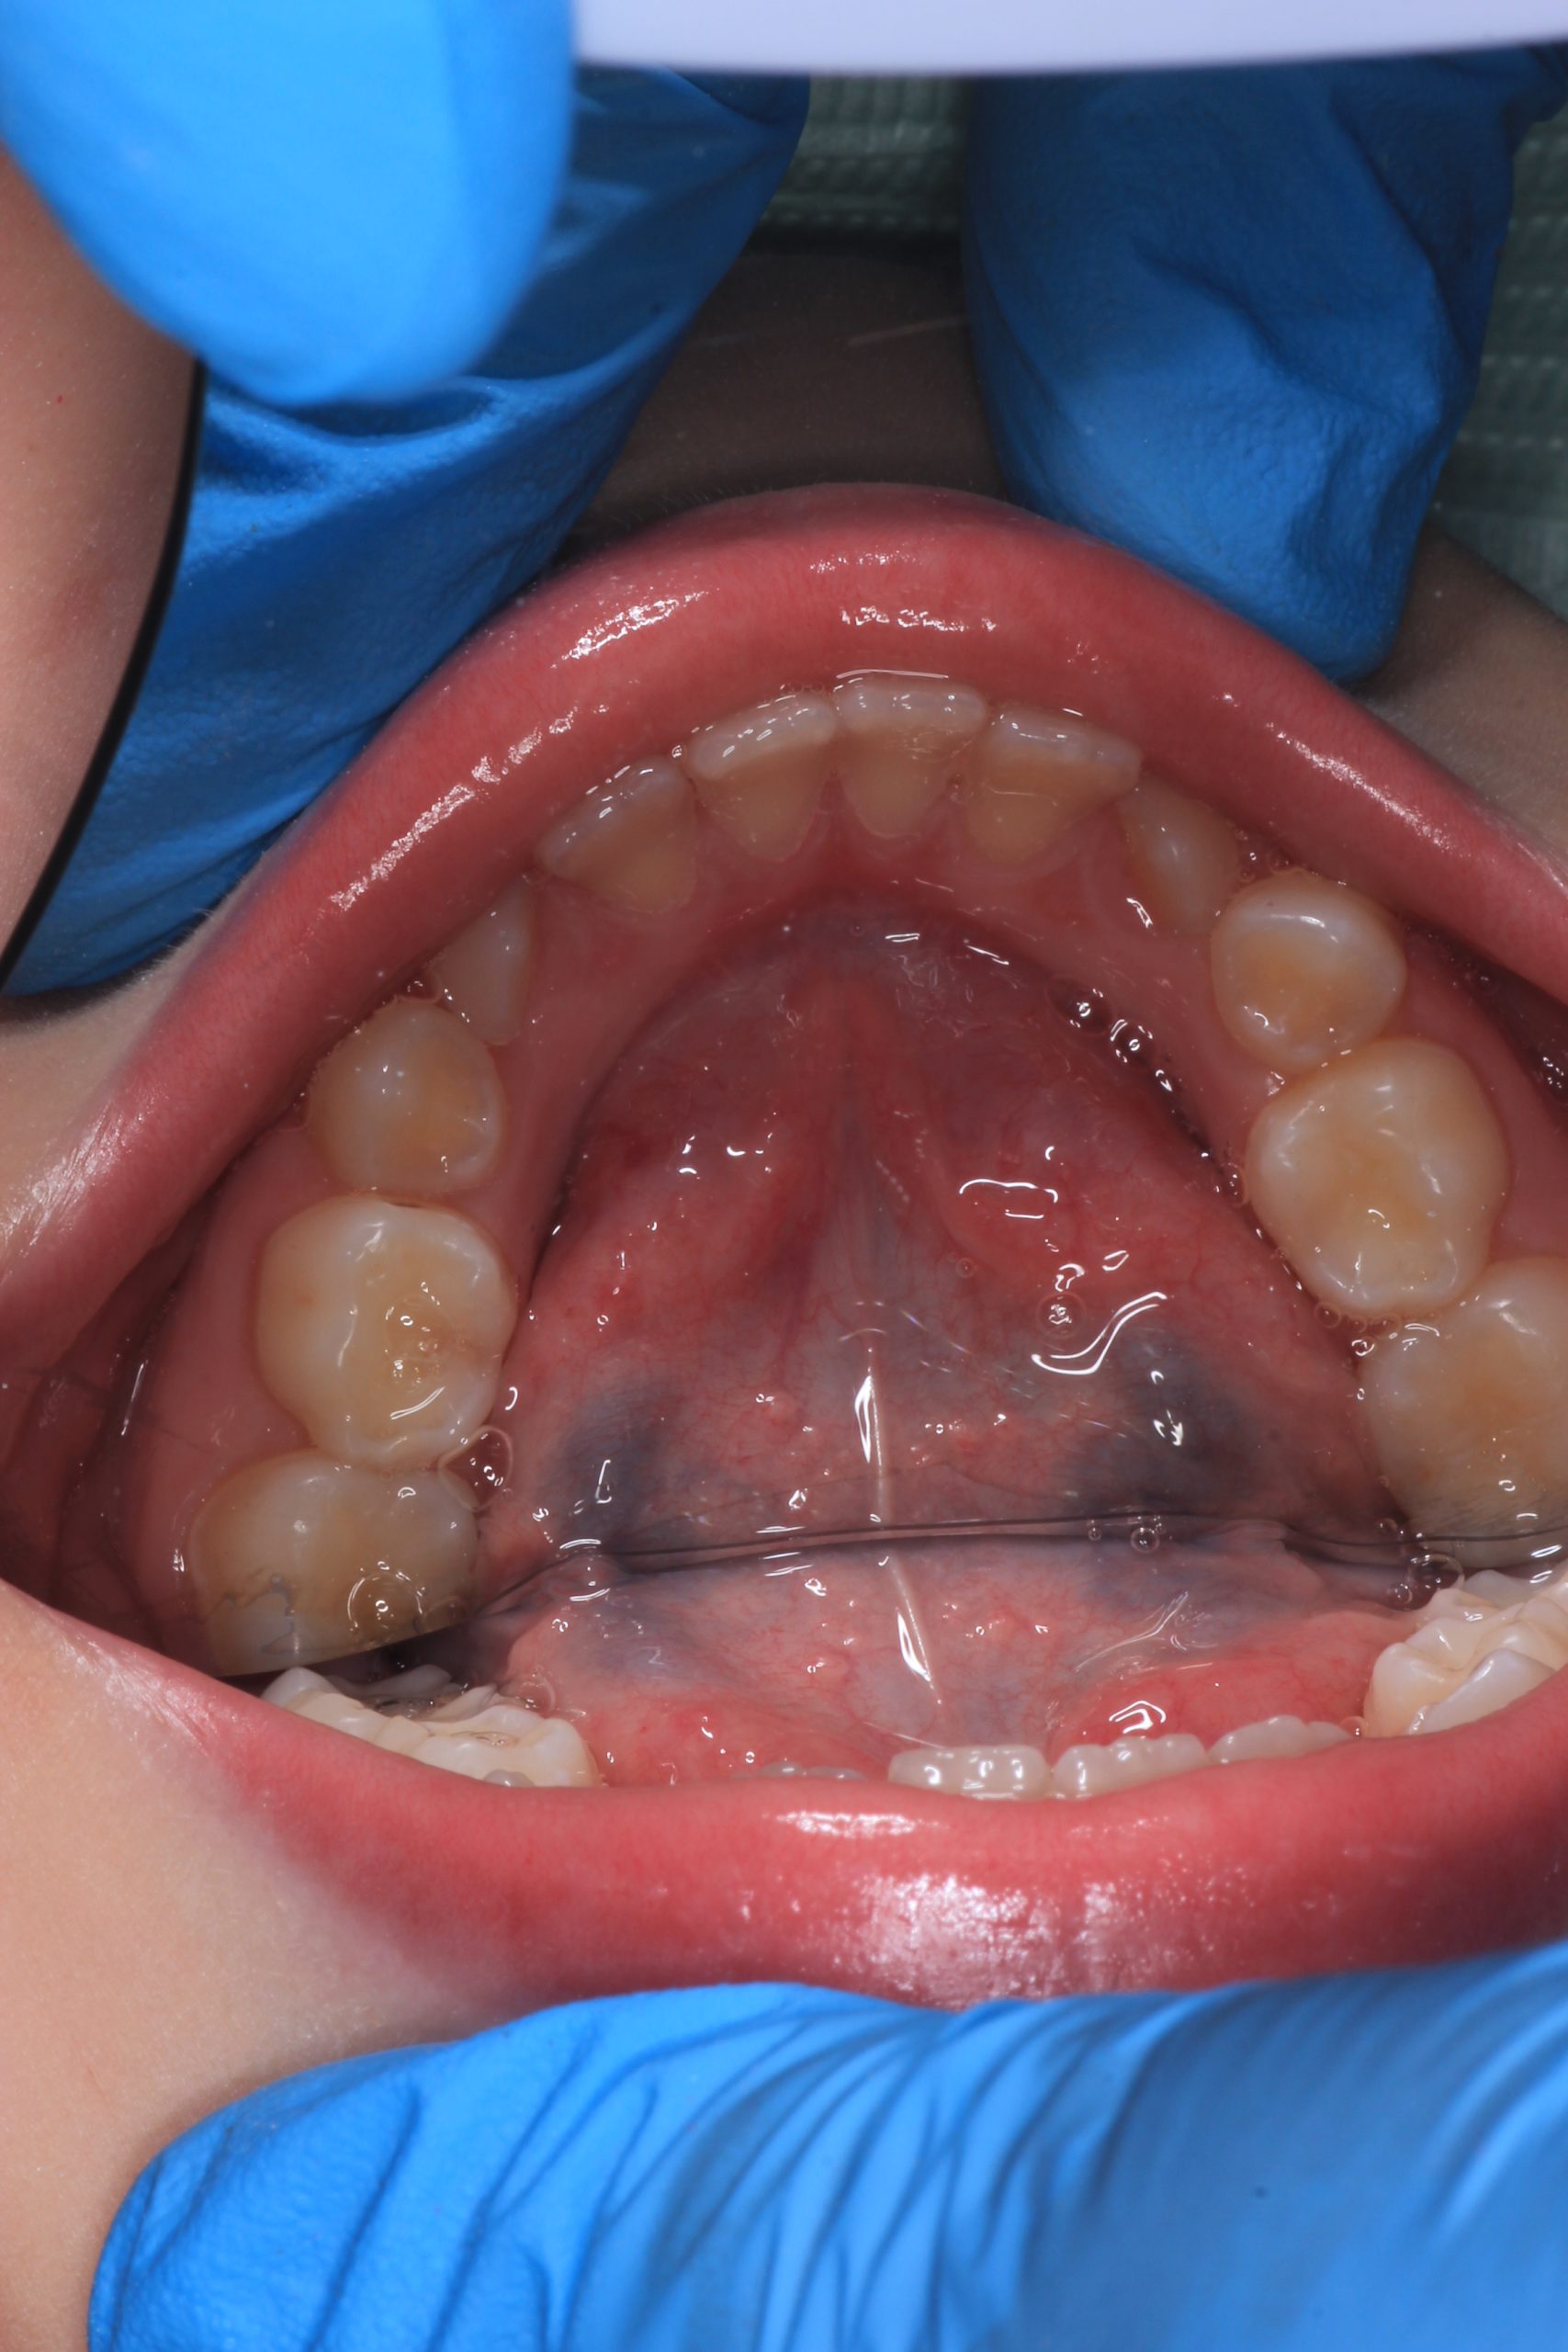

GBT (Guided Biofilm Therapy) is a modern, safe protocol for professional dental cleaning developed in Switzerland. For children, we use it to gently remove plaque, prevent cavities, and teach proper brushing — with plaque-disclosing dye and AirFlow technology starting from age 4–5.

Together with your child, we practice brushing techniques, correct mistakes, and provide personalized recommendations. We advise whether to use manual or electric brushes, floss, interdental brushes, or remineralizing gels. - Plaque Removal with AIRFLOW Prophylaxis Master (EMS, Switzerland)

From age 4–5 and up, we perform full GBT cleaning using an ultra-fine erythritol powder to clean even hard-to-reach areas gently and safely. It does not damage enamel and is ideal even around braces — no need to remove brackets or wires. - Tartar Removal (If Needed)

Any tartar is removed gently and painlessly. - Final Check-Up + Fluoride Protection

We ensure the teeth are clean and free from early caries (even in the spot stage), then apply fluoride varnish to protect and strengthen enamel. - Personalized Recall Plan